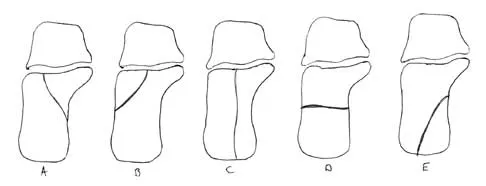

A patient who sustained a knife wound to the axilla 4 months ago now has profound interosseous wasting and generalized hand weakness. A brachial plexus injury is likely at which of the following locations in Figure 29?

Explanation